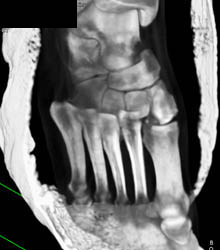

Subtle Talus Fracture